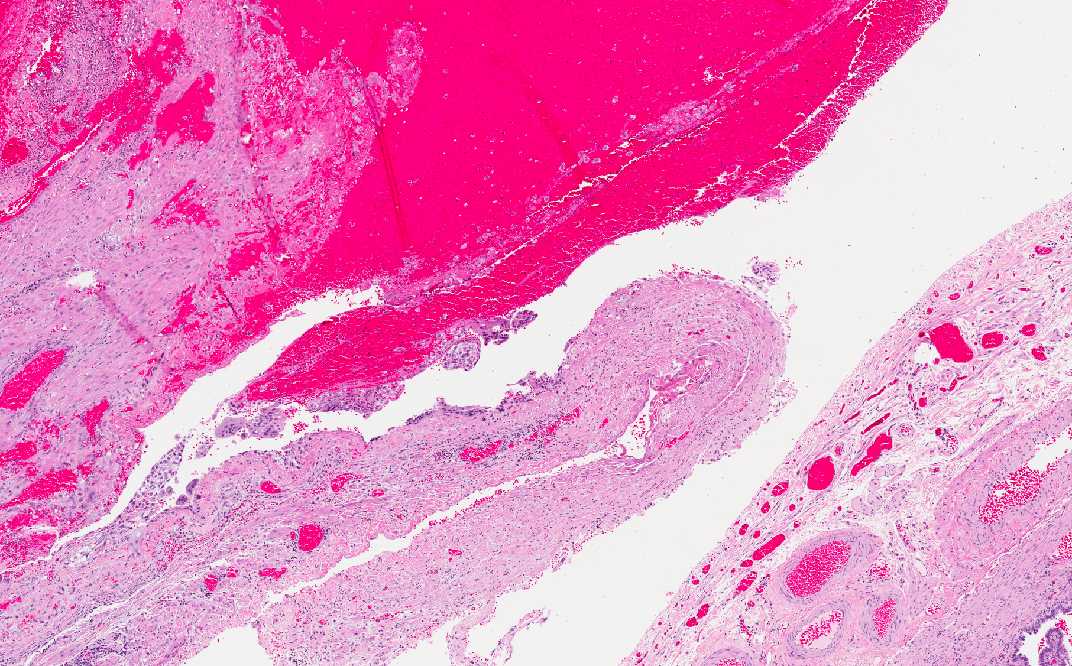

• The fallopian tube is filled with fallopian tube and the wall of the fallopian tube is compressed by the hematoma. In some of the cases, the tube may rupture.

Area 2: Note that the hematoma has expanded the fallopian tube (compare the diameter of the two sections) and that the wall of the fallopian tube is thinned.